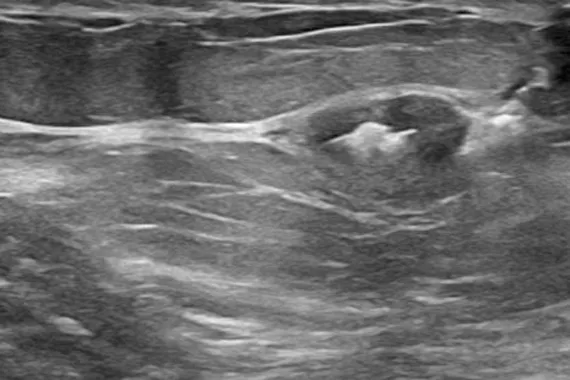

Marcatori del sito bioptico SecurMark®

Studiati per contenere al minimo la migrazione,2 questi marcatori sono perfettamente visibili in ecografia al momento dell'applicazione e rimangono ben identificabili anche dopo 6 settimane dalla biopsia, un fattore essenziale in caso di futuri interventi sulla mammella.3 Ogni marcatore è composto da due parti, un marcatore permanente e una rete bioassorbibile in materiale analogo al filo per sutura.